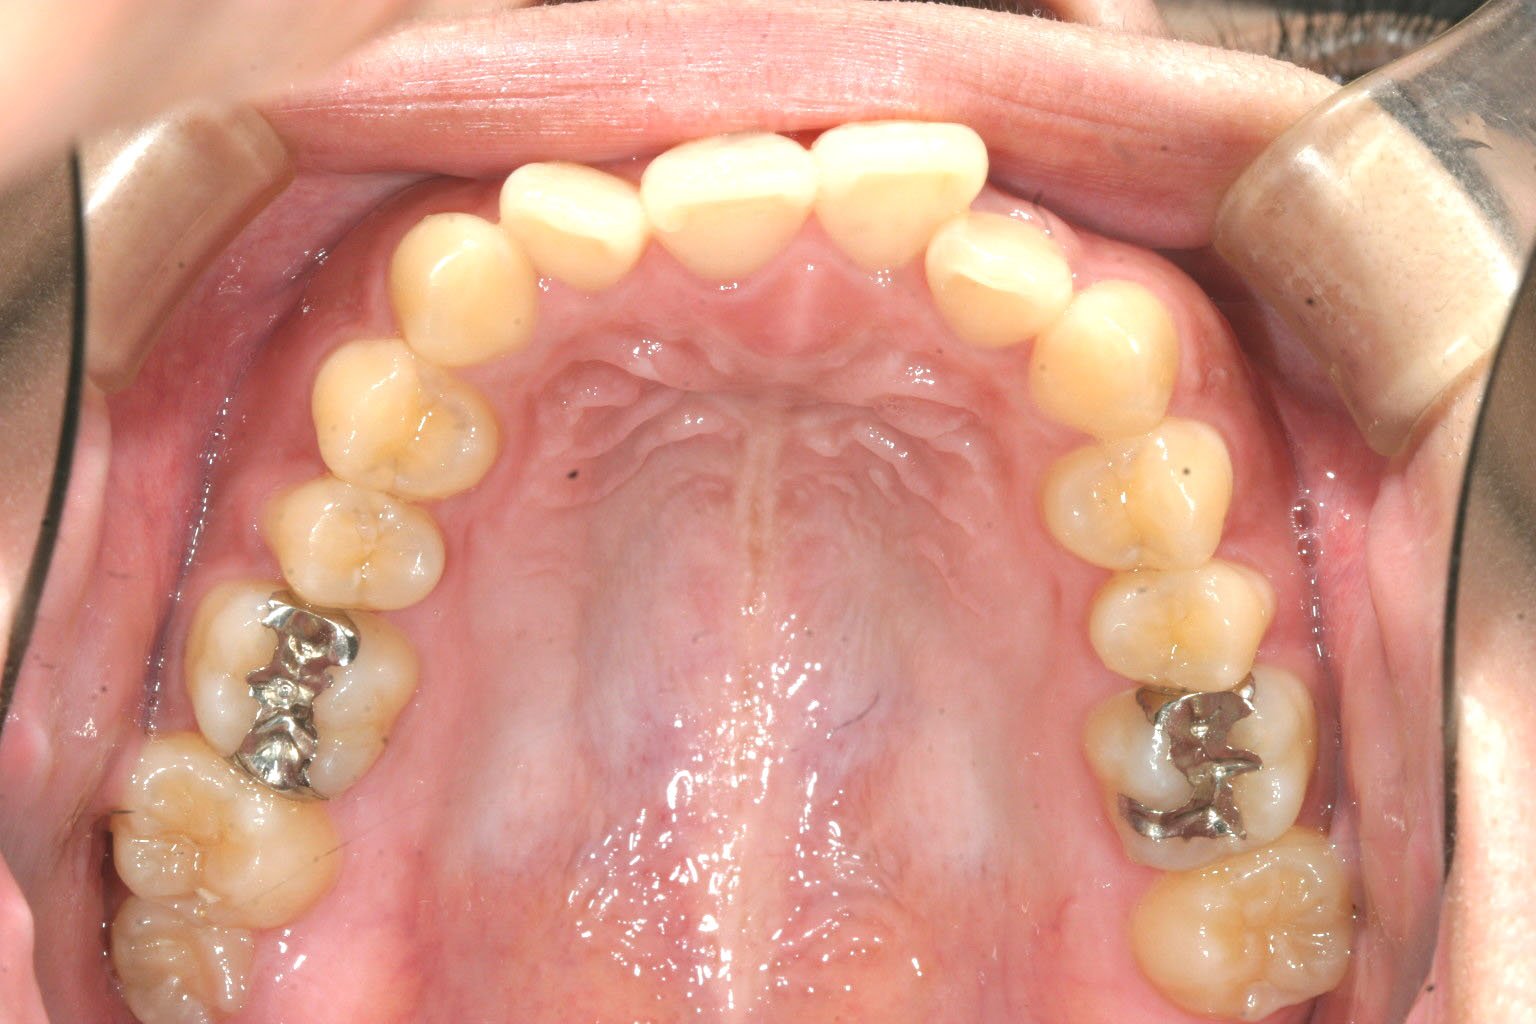

左の前歯が大きく捻転し飛び出ています。

アーチを少し拡大し綺麗に並べてみました。